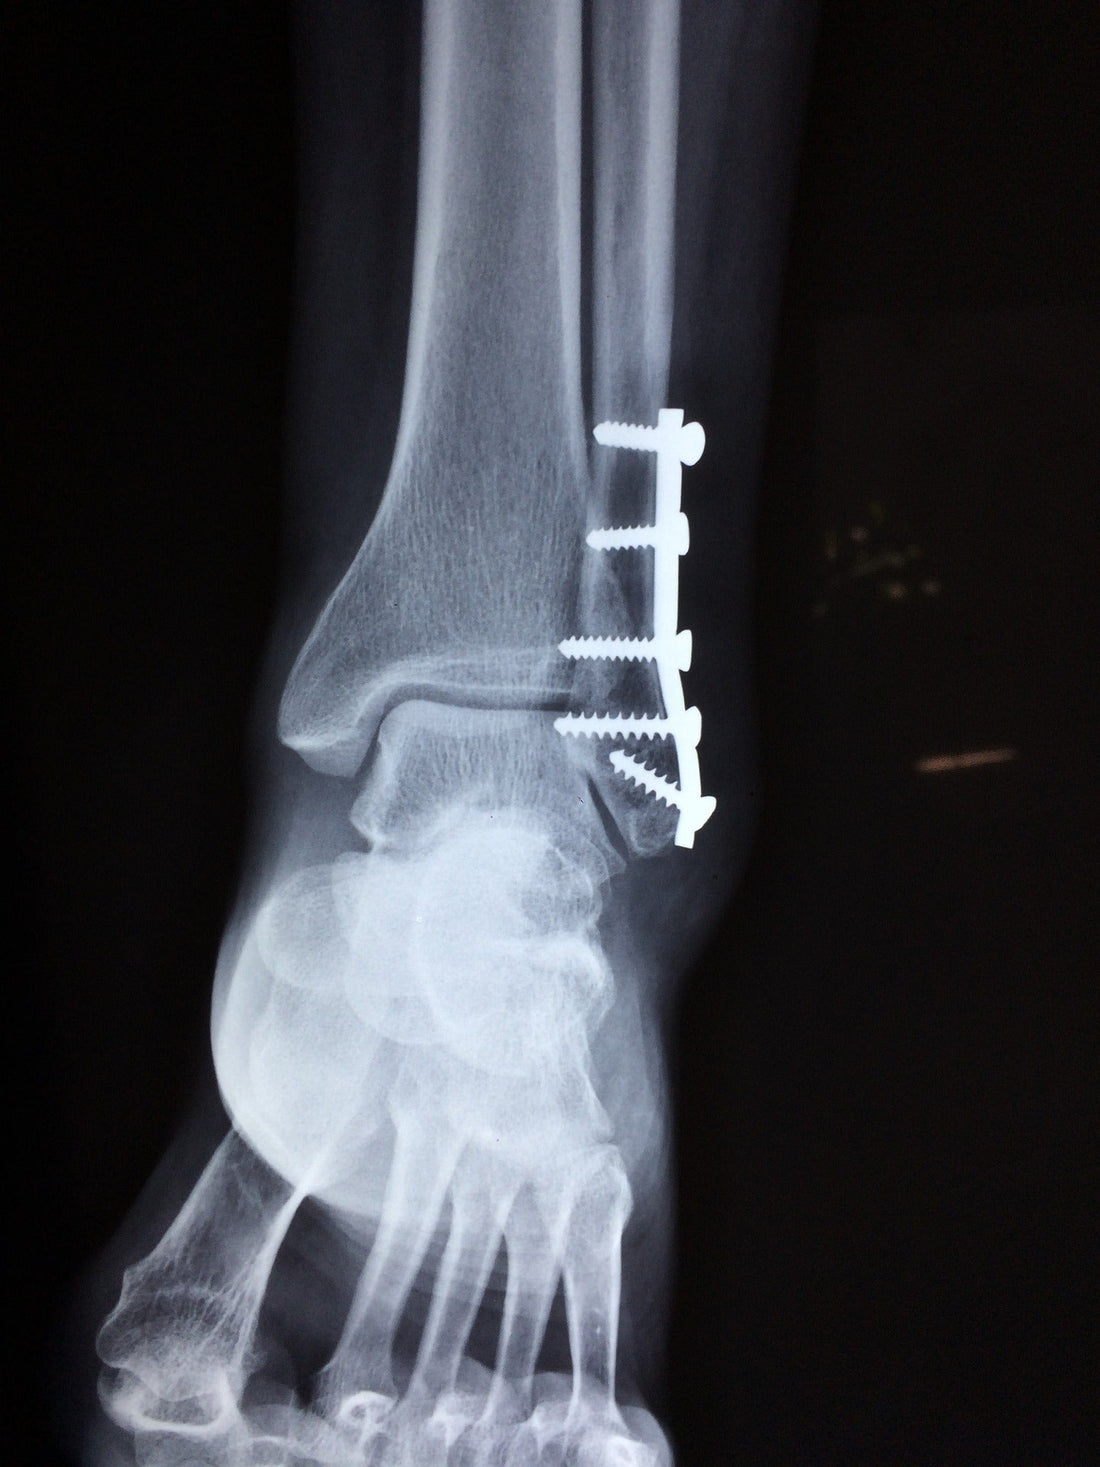

- Ankle fracture surgery - The broken bone fragments are moved back to the correct position inside the ankle and stabilizing items, such as screws and metal plates, are inserted to support correct healing.